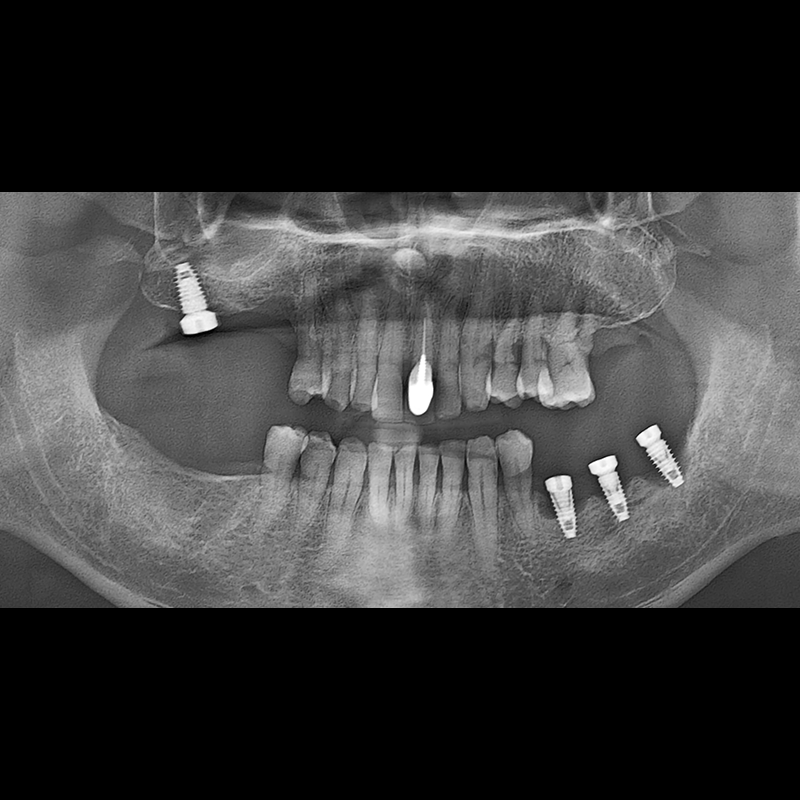

インプラント手術事例 2025.05.30

欠損した歯の部分と、生かしにくい歯の位置にインプラントを植立しました。